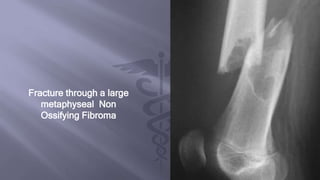

Fracture through a large

metaphyseal Non

Ossifying Fibroma

Radiographs demonstrated an

osteolytic lesion with sclerotic

margins, mild expansion, and

central calcification

Fracture through alarge metaphyseal Non Ossifying Fibroma

Radiographs demonstrated an osteolyticlesion with sclerotic margins, mild expansion, and central calcification